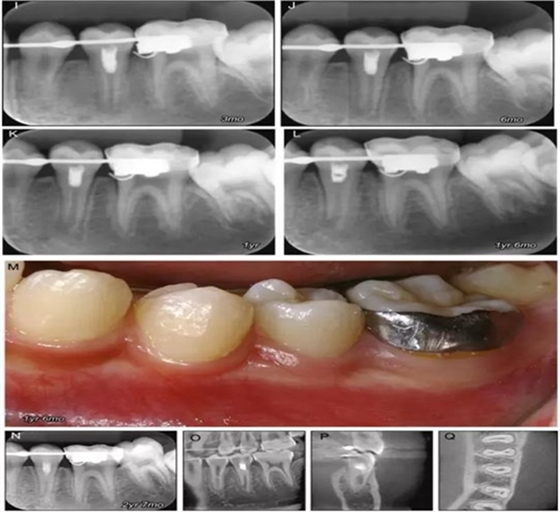

原則上年輕恒牙的牙髓治療應(yīng)盡可能以保存活髓的方式以便不影響牙根繼續(xù)發(fā)育。本文3個病例均描述了根尖尚未發(fā)育完成的下頜前磨牙被確診為牙髓壞死伴有大面積根尖病損,治療過程中在根管內(nèi)發(fā)現(xiàn)了部分活髓,而采用活髓切斷后都取得了很好的療效。